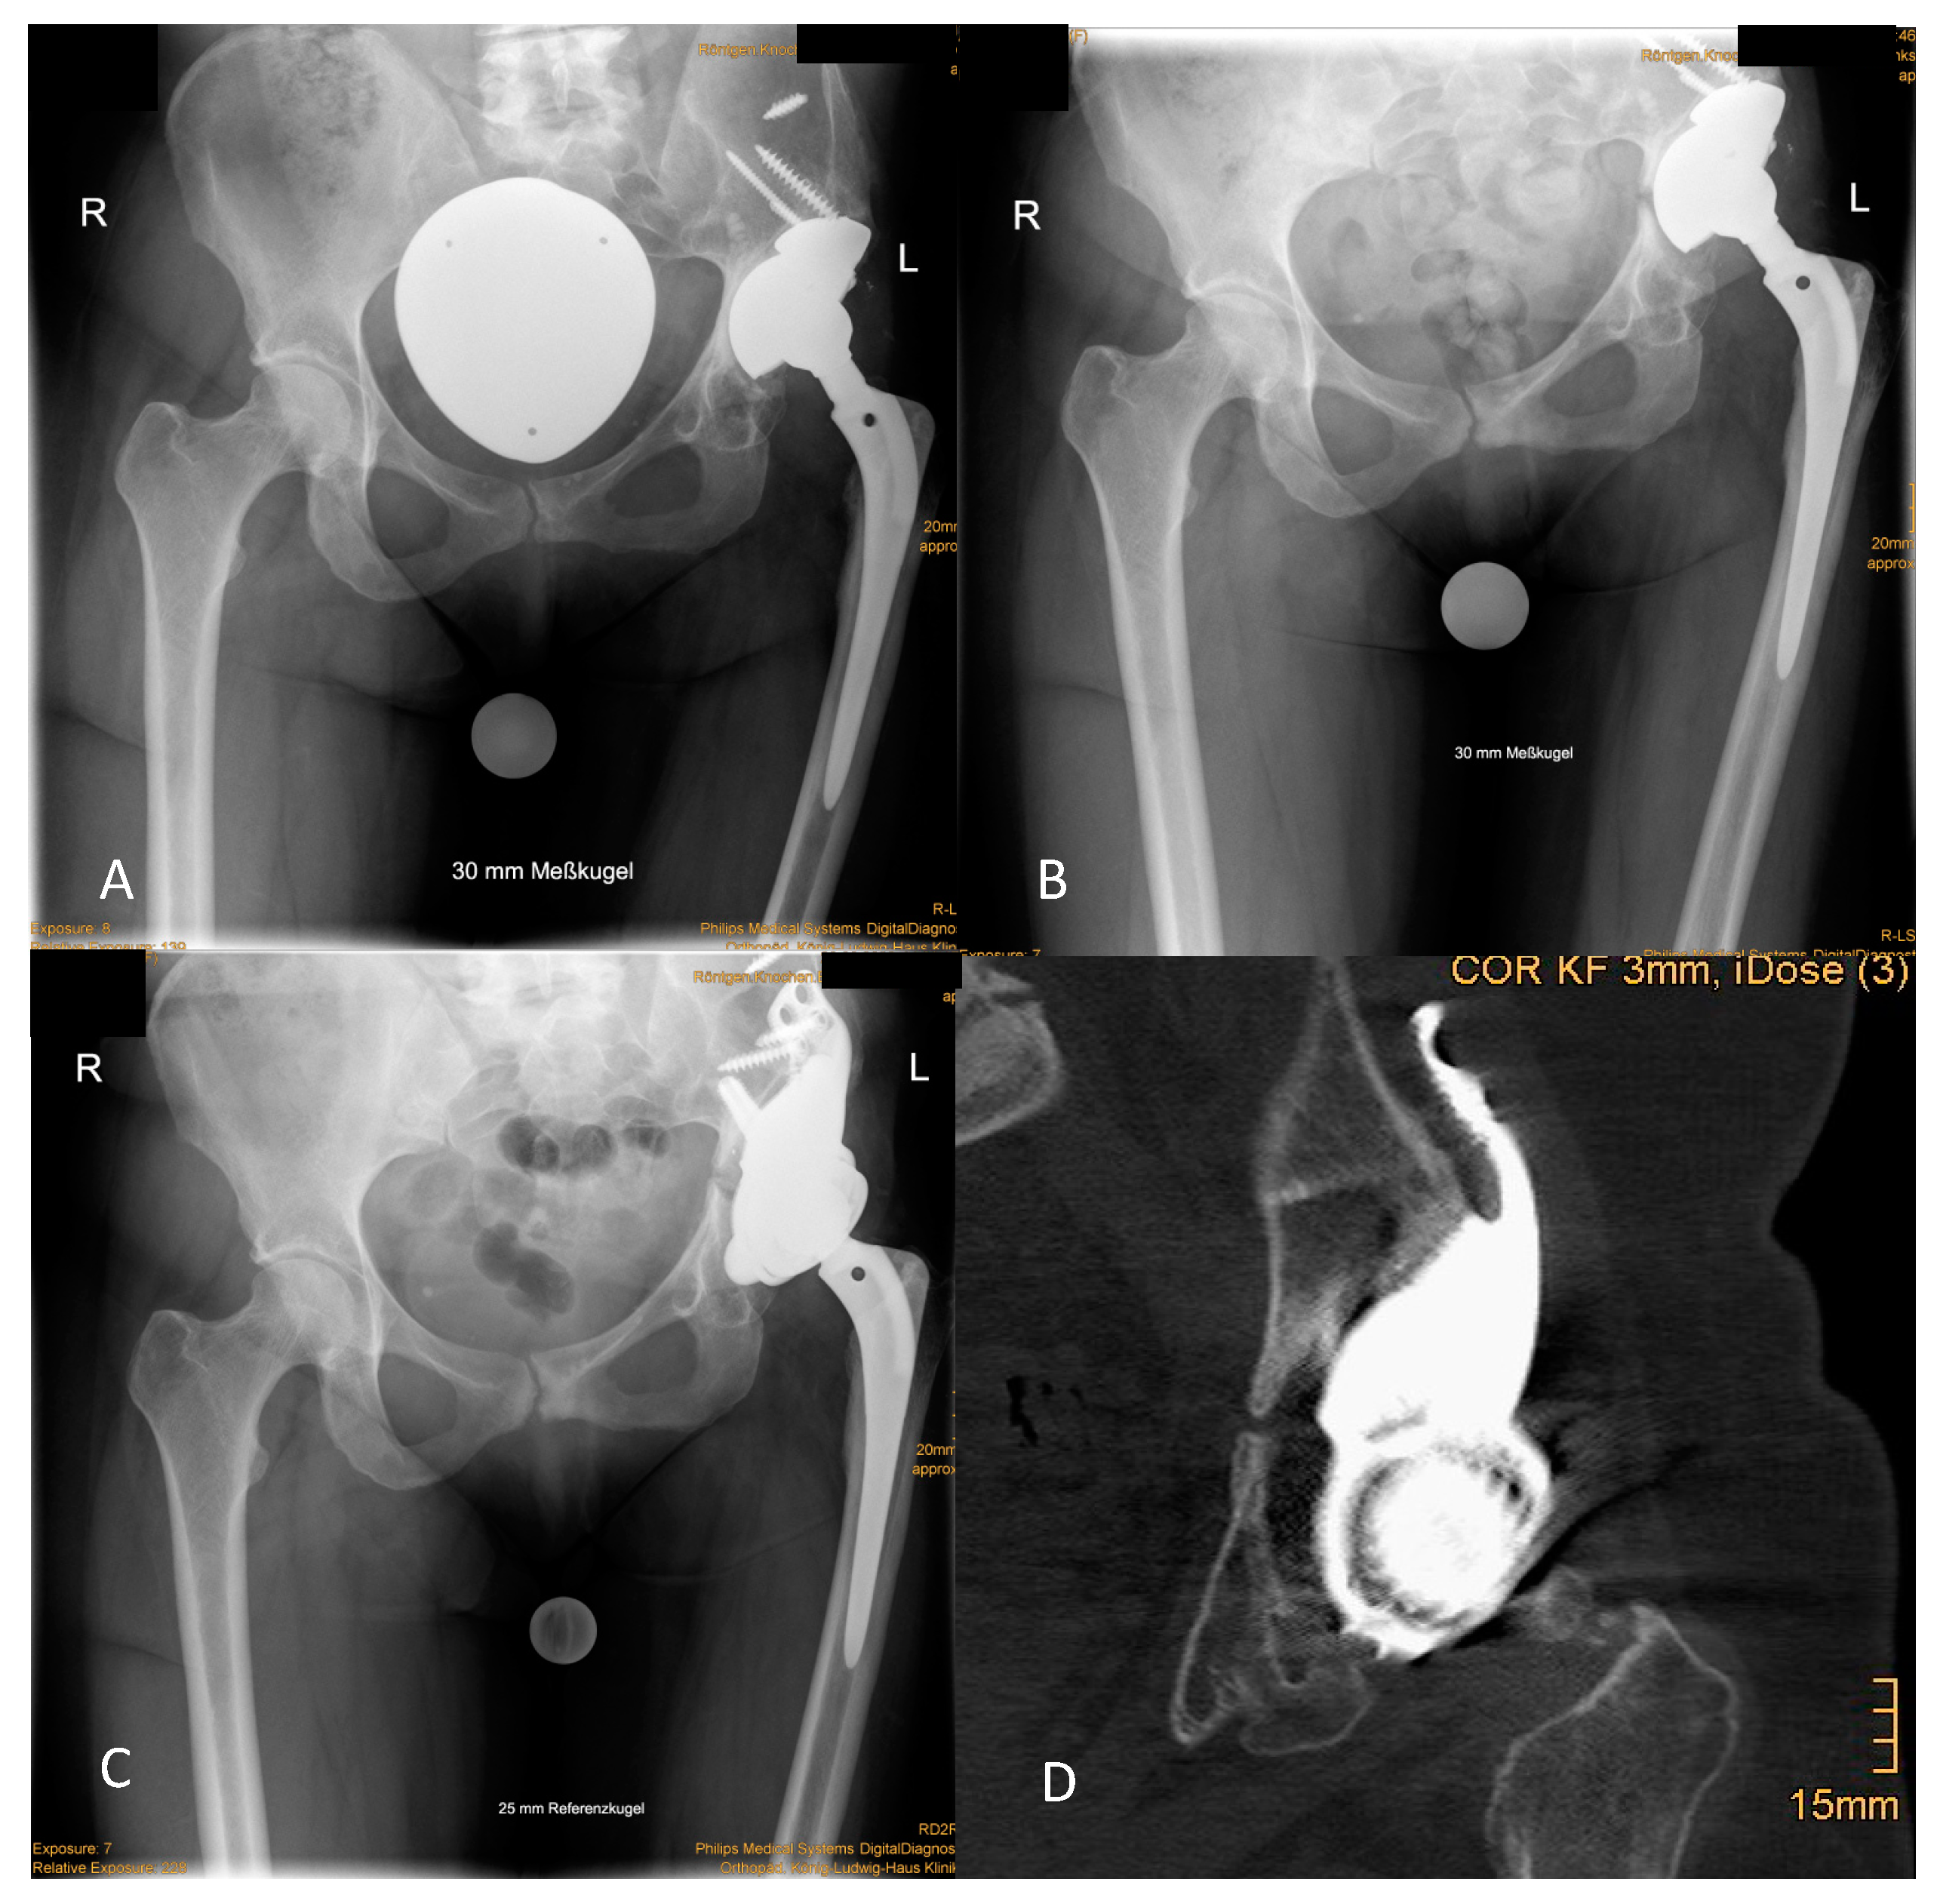

Results of radiographic evaluation are shown in Table 3. Two patients were planned with intentional extra-anatomic reconstruction of COR as depicted in Figure 3 and Figure 4.

The reported outcome is certainly influenced by patient-related presuppositions for acetabular reconstruction, which are anteceding or even subliminal infection and massive bone loss. In the current study, all patients had at least a Paprosky type III acetabular defect and 42.86% of patients even displayed PD. The optimal surgical strategy for those patients has not yet been defined. A stable pelvic ring is discussed as the “conditio sine qua non” for prevention of mechanical failure of acetabular constructs [7]. Antiprotrusion cages and CTACS as well as cup cage constructs aim to fulfill this strategy [14]. In contrast, the presented implant design abandons this strategy and relies on a combination of intra- and extramedullary iliac fixation for primary stability. However, positioning of the stem can be challenging. In two cases with a IIIa defect but with sufficient medial abutment by the remaining bone, the stems were dispensed. Implant loosening was not observed in these cases. However, whenever possible the iliac stem should by applied for optimal fixation. A rigid fixation of the CMAC to the Os ilium allows osteointegration as depicted in postoperative CT scans (Figure 4).

Figure 4. Osteointegration of the socket at follow-up. (A) Preoperative situation demonstrated an “up and out” defect that was filled by the loosened cup and augment construct. (B) The radiographic control after 2 years displayed PD with complete disruption of the ilio-ischial line and medial protrusion of the cup. (C) Radiographic situation 2 years after revision showed no sign of loosening. (D) In the CT, spot welds, as sign of osteointegration at the HA-coated socket, were seen.